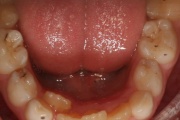

Lutipudelikaariese kahjustused

Lutipudelikaaries